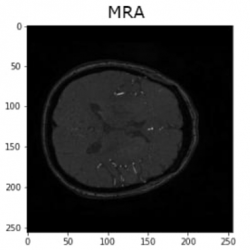

IXI dataset: Upon reviewing and analysing the entire IXI dataset, it was observed that there are 2 contrasts that exist in different templates from the remaining. The middle original slices of the 4 contrasts are shown in Fig.

10:

Illustration of axial slices of IXI dataset before registration.

As depicted in Fig.

10, it is evident that MRA images are in shapes (512, 512, 100), while T1 images are in completely different templates (size and plane). However, it is noteworthy that there are still PD and T2 images in the same template and similar to BraTS2020 images. In light of this observation, the decision is made to apply some registering transformations to MRA and T1 images using the common template synthesized from PD and T2. For this experiment, an affine transformation is employed from the AntsPy package (Avants